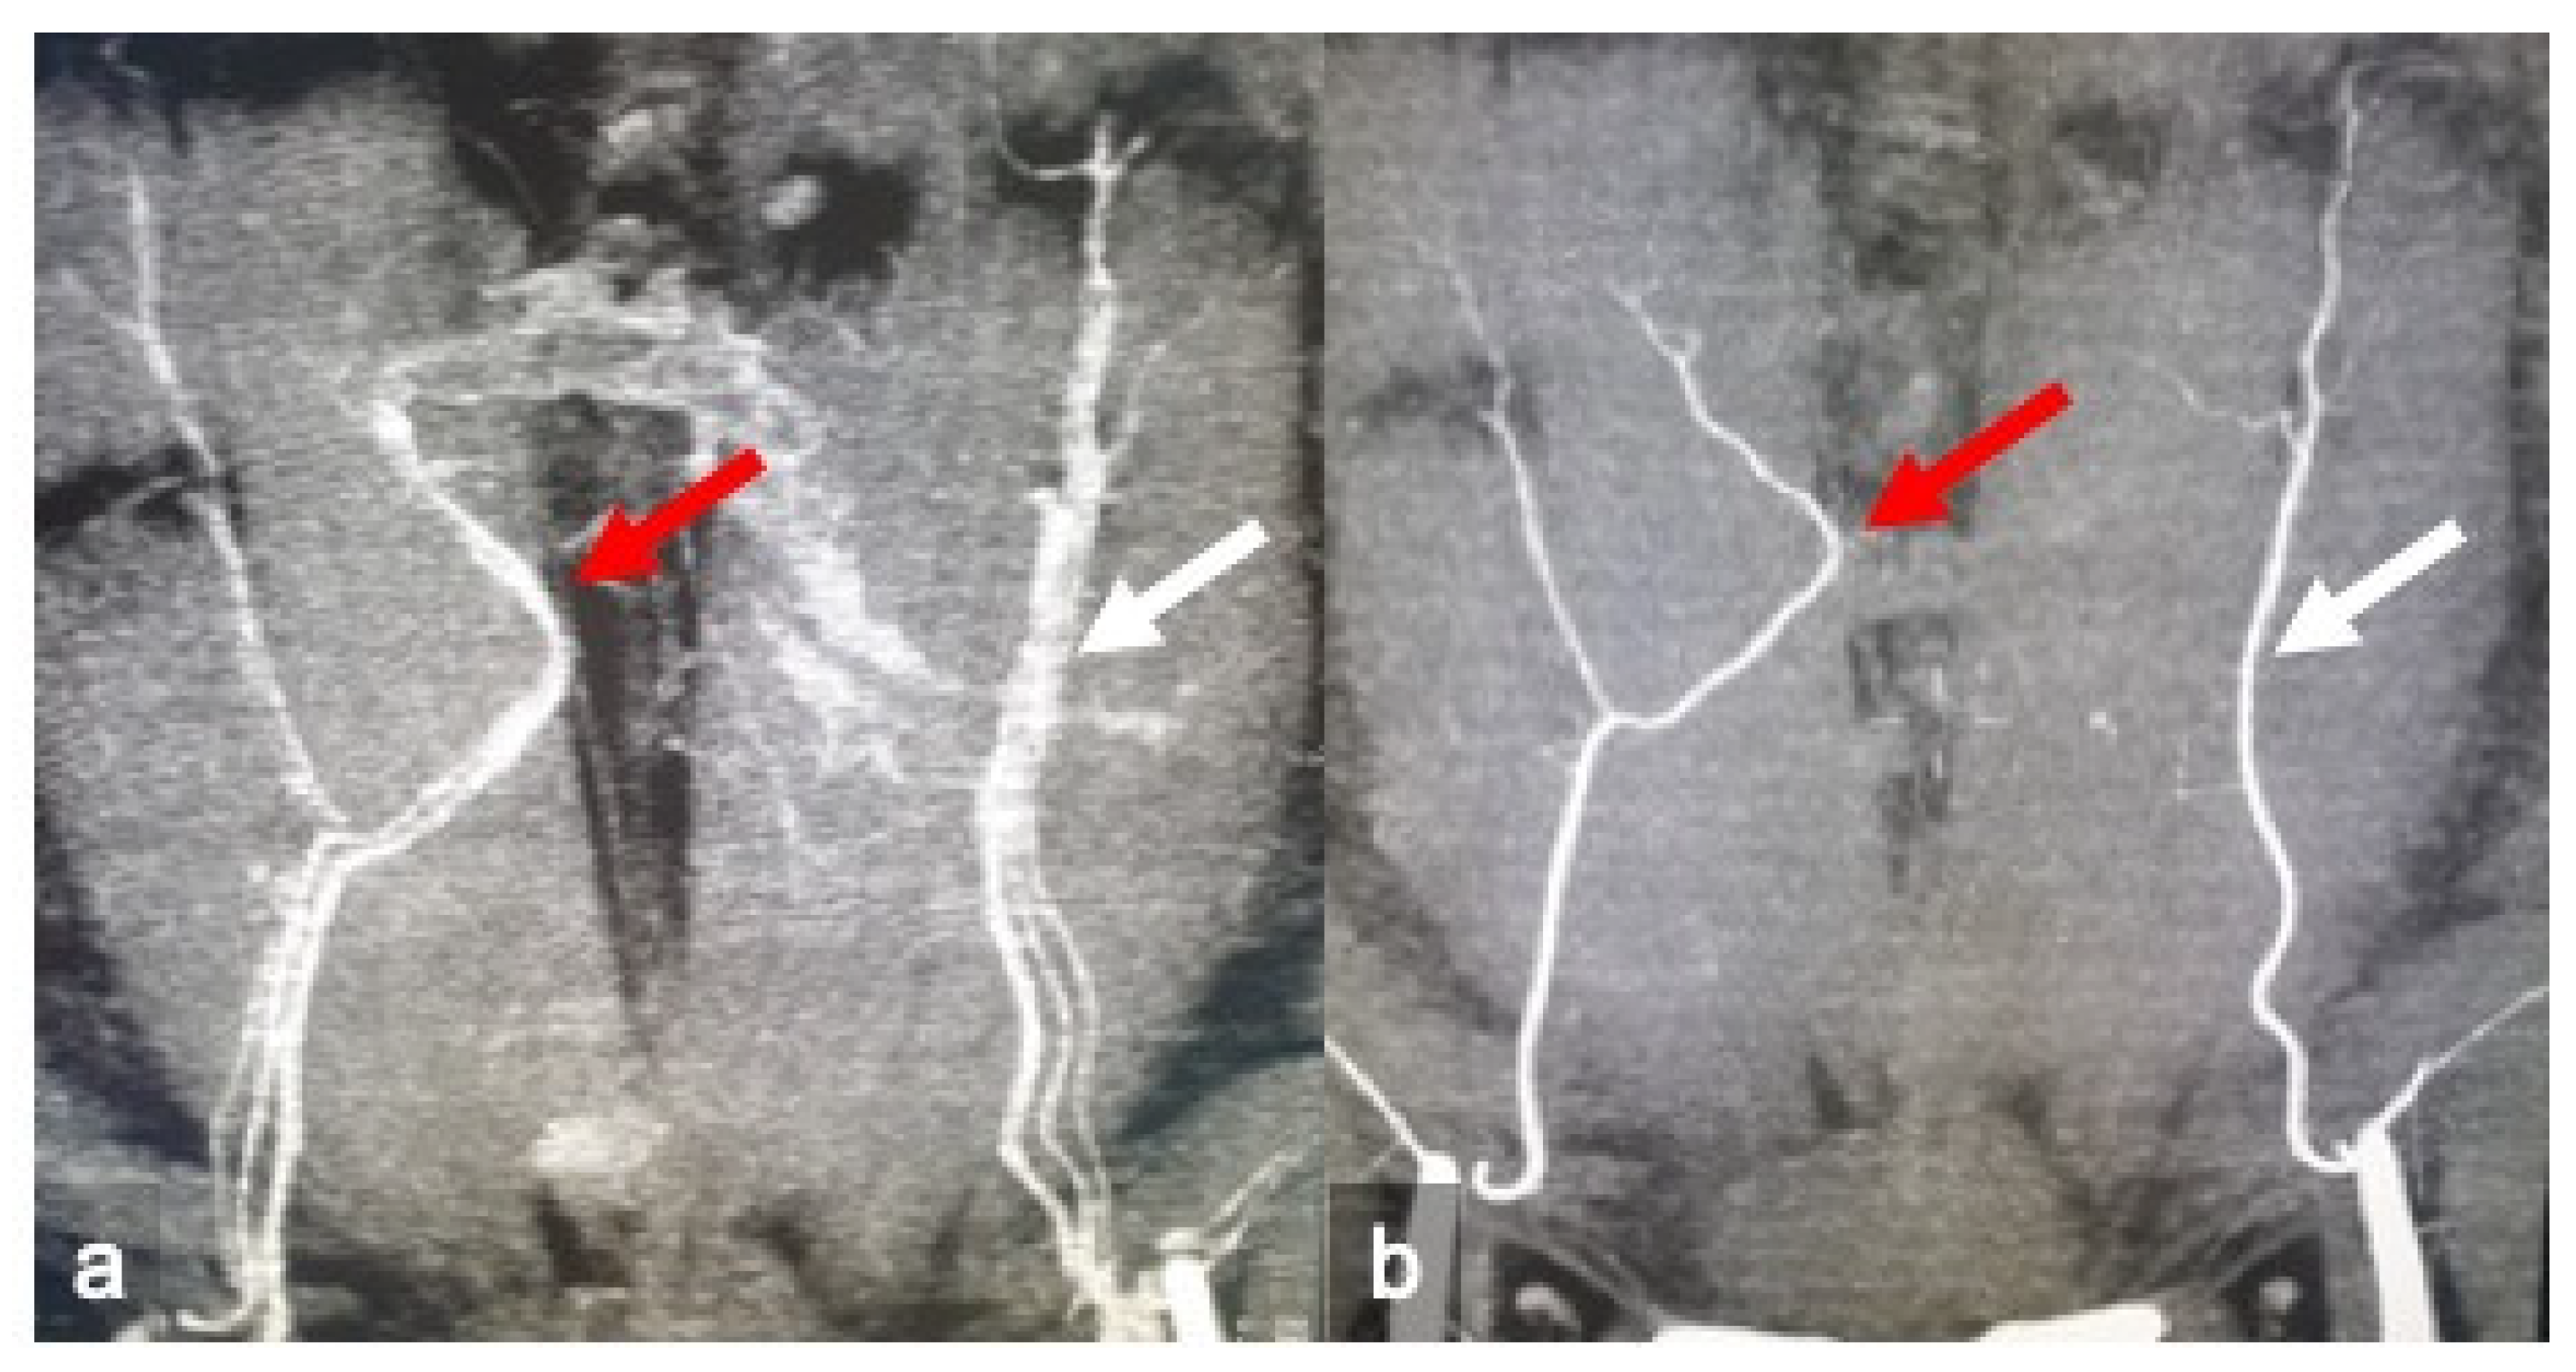

2. Materials and Methods

2.1. CTa and cCT Technique

2.2. Image Analysis

3. Results

4. Discussion